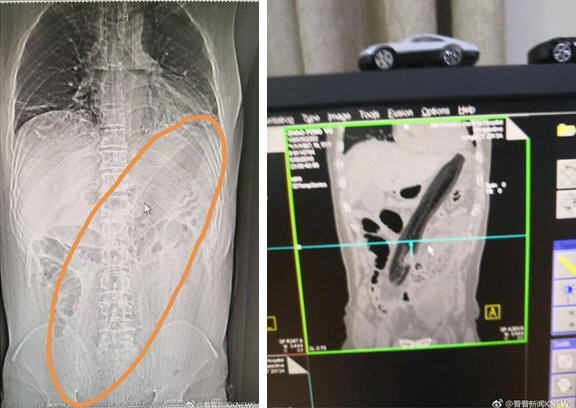

Hình ảnh chụp ích quang vị trí quả cả tím trong cơ thể người đàn ông.

Tại bệnh viện, hình ảnh X-quang cho thấy quả cà tím khổng lồ được đẩy vào mông người đàn ông đã gây ảnh hưởng đến phổi. Các bác sĩ tại bệnh viện phải tìm cách để rút dị vật ra ngoài. Tại đây, người ta đo được quả cà tím dài đến 30cm.

Quả cà tím dài 30 cm.

Vào tháng 5 vừa qua, một người đàn ông sống tại Quảng Châu, Trung Quốc đã suýt chết khi bị một con lươn dài khoảng 50cm phá vỡ ruột và làm sưng dạ dày từ bên trong. Khi được đưa đến bệnh viện trong tình trạng nguy kịch, người này giải thích bản thân đã nhét lươn vào hậu môn dựa theo bài thuốc dân gian trị táo bón.